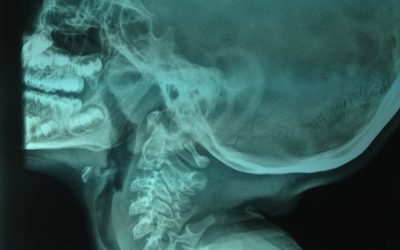

From Need for Hearing Aids to Almost Normal Hearing

This 30 plus patient had history of failed ear surgeries in the past and had come with lots of hopeHe had a huge ear drum perforation and was advised hearing aids, felt depressed and came for an opinion. I advised Cartilage Tympanoplasty and the results speak. ...